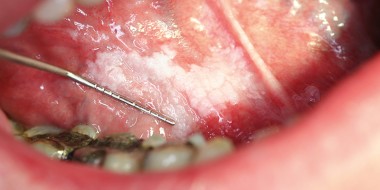

HPV-positieve orofarynxtumoren presenteren zich, vaker dan HPV-negatieve tumoren, als kleine (asymptomatische) tumoren die vaak al gemetastaseerd zijn naar de cervicale lymfeklieren.